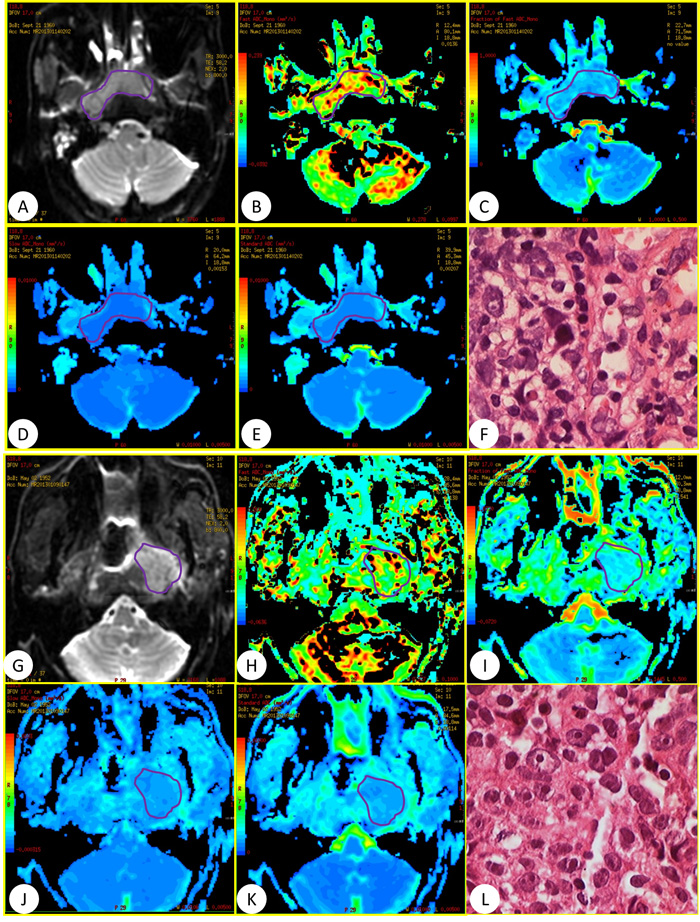

General MRI and IVIM were successfully performed in the 60 patients using 3.0-T whole-body system (Signa EXCITE HD, GE Healthcare, Milwaukee, WI, USA) before and after standard regimen of IMRT. The images of general MR sequence were showed in Figure 1. IVIM images and representative pathological slides of biopsy for both effective groups and poor effective groups were showed in Figure 2. The mean largest diameters of tumor (± SD) in patients with NPC before and after IMRT were showed in Figure 3, respectively.

Figure 2: (A–F) Was a 52-year-old man in effective group and (G–L) was a 60-year-old women in poor effective group who referred to our department for confirmation of the NPC diagnosis. IVIM with 13 b values (in the range 0–800 s/mm2) was performed before standard regimen of IMRT. (A and G) DWI image, (B and H) D*, (C and I). f , (D and J) D, (E and K): ADC parameters, (F and L) pathological slides.

In IVIM theory, D* is related to perfusion depended on tumor microvessel attenuation. Furthermore, the value of D* was determined according to the signal intensity ratios of the blood capillaries. In our study, the mean D* value for primary NPC was in agreement with a previous study on metastatic nodes by Lu et al.[16]. D* is large greater than D, which explains why D* has a stronger influence on signal decay when b < 200 s/mm2. Our results showed a significant increase in D* (mean, 152.96×10-3 mm2/s vs. 120.36×10-3 mm2/s; P<0.0001) for effective group than poor effective group. This may result from the differences of histologic structure in the NPC tumor with or without abundant vessels. From the pathological slides of biopsy for the effective group, we found that there was much more neovascularization than the poor effective group. The neovessels could transport the blood and oxygen to the tumor lesions and improve the hypoxia. Obviously, the value of D* in effective groups was higher than poor effective groups, which might result from the more neovascularization in effective groups. Interestingly, the degree of capillary could be revealed by the degree of MRI enhancement in patients with NPC [34]. D* was considered to be proportional to the mean capillary segment length and average blood velocity [9]. So, slow blood velocity and small capillary segment length corresponded to low D* values. While the inadequate blood feed due to the slow blood velocity and small capillary segment length would cause the hypoxia of tumor microenvironment and poor radiosensitivity. Therefore, the increased D* value was proportional to the higher effective radiosensitivity. And D* may be an indicator for evaluating the radiosensitivity of NPC.